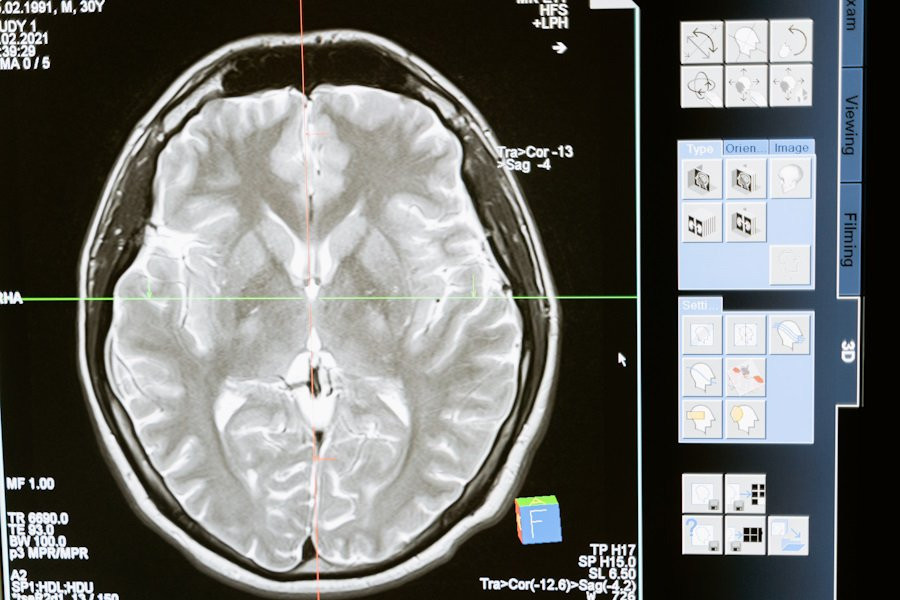

Гематоэнцефалический барьер — это высокоселективная мембрана, которая отделяет кровь от мозга и защищает его от вредных веществ. Преодоление этого барьера долгое время было серьёзной проблемой для учёных, разрабатывающих безопасные и эффективные методы генной терапии.